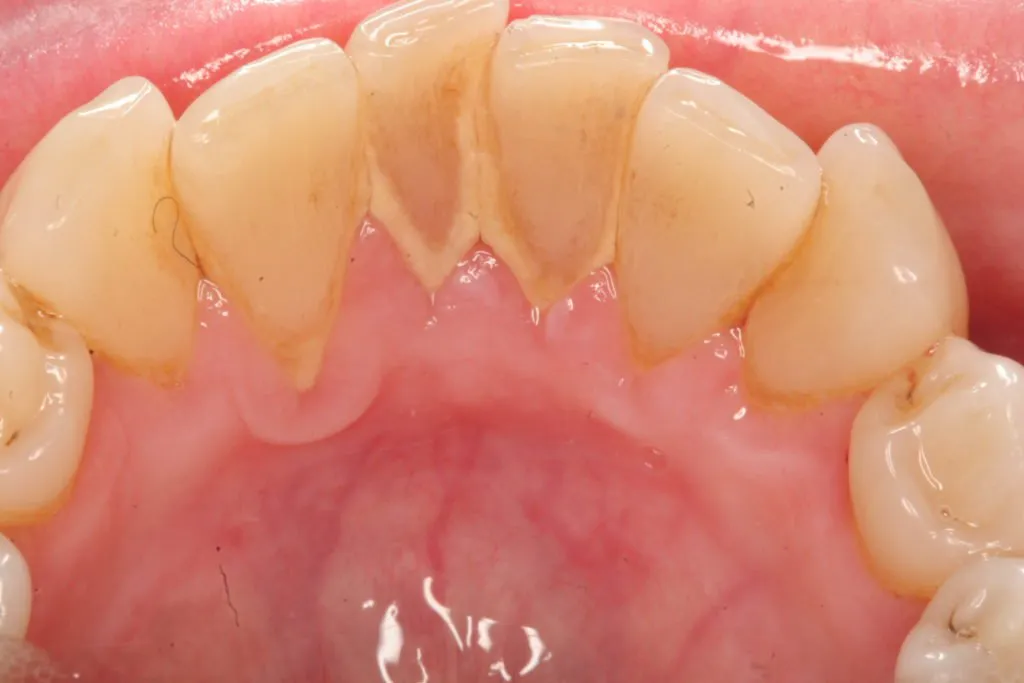

Cao răng (vôi răng) hình thành do mảng bám tích tụ bị vôi hóa bởi các hợp chất muối vô cơ. Cao răng nhiều và sẫm màu hay còn gọi là cao răng huyết thanh. Đây là tình trạng cao răng nặng, ở cấp độ 3 hoặc 4.

Cao răng dày hình thành do cao răng thông thường lâu ngày không lấy, tích tụ lại đóng thành mảng dày. Đây là loại cao răng thường gây viêm lợi vì cao răng dày xâm lấn vào lợi gây chảy máu. Máu ngấm vào cao răng tạo màu nâu đỏ nên gọi là cao răng huyết thanh.

Bởi vậy nên nếu bạn thấy có cao răng bám dày trên răng thì nên xử lý ngay. Tránh tình trạng hình thành cao răng để lâu có màu nâu đỏ, gây ra nhiều vấn đề nguy hiểm ảnh hưởng đến sức khỏe răng miệng.